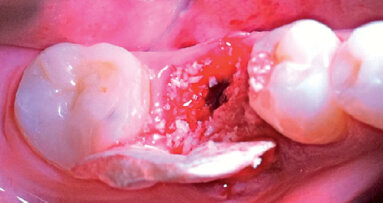

In questo articolo presentiamo un caso clinico che dimostra come il posizionamento improprio di un impianto può rendere impossibile la riabilitazione protesica, che richiede una nuova pianificazione chirurgica e riabilitativa per ottenere l’estetica desiderata. La paziente si presenta alla nostra osservazione con una riabilitazione protesica incongrua, con flangia in resina, a supporto dentale ed implantare, con la presenza di un impianto in posizione 2.1 vestibolarizzato e con l’emergenza nel fornice, in mucosa alveolare. Dalla valutazione della Tac si evince la posizione errata dell’impianto e la perdita consistente in senso trasversale della compagine ossea (Figg. 1, 2). Pertanto si opta per il seguente piano di trattamento che prevede: rimozione dell’impianto e preparazione protesica dell’elemento 2.3, confezionamento di un primo provvisorio a supporto dentale che servirà a guidare la guarigione dei tessuti (Figg. 3-7). A distanza di 4 mesi si procede a un innesto epitelio connettivale libero con prelievo dal palato per compensare il gap dei tessuti molli in senso trasversale, quindi viene ribasato il provvisorio in modo tale da favorire la guarigione dei tessuti (Figg. 8-11). A 9 mesi dalla maturazione dei tessuti si procede alla finalizzazione protesica fissa a supporto dentale (Figg. 12-14).

Fig. 8 - Innesto di epitelio connettivale libero dopo 4 mesi dalla guarigione del sito implantare.